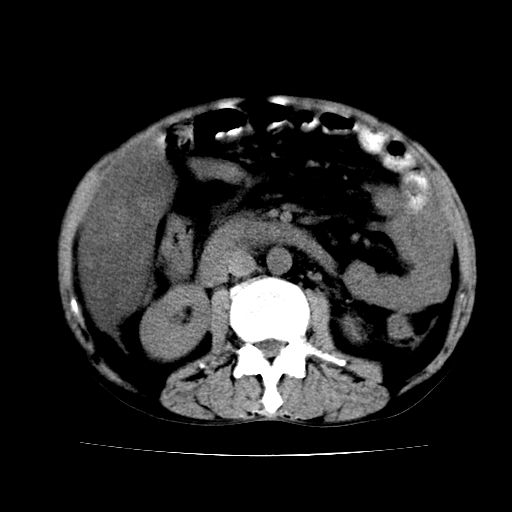

男,55岁,发现“肝硬化”5年,现腰疼、腹胀10余日,巩膜黄染、腹稍胀,肝肋下3指,质硬无压疼,移动性+,血生化:总胆、直胆、间胆均升高。

1.脂肪肝

2.腹水

3.肝脾肿大

4.肝癌?

建议增强

肝硬化,脂肪肝,腹水,肝癌